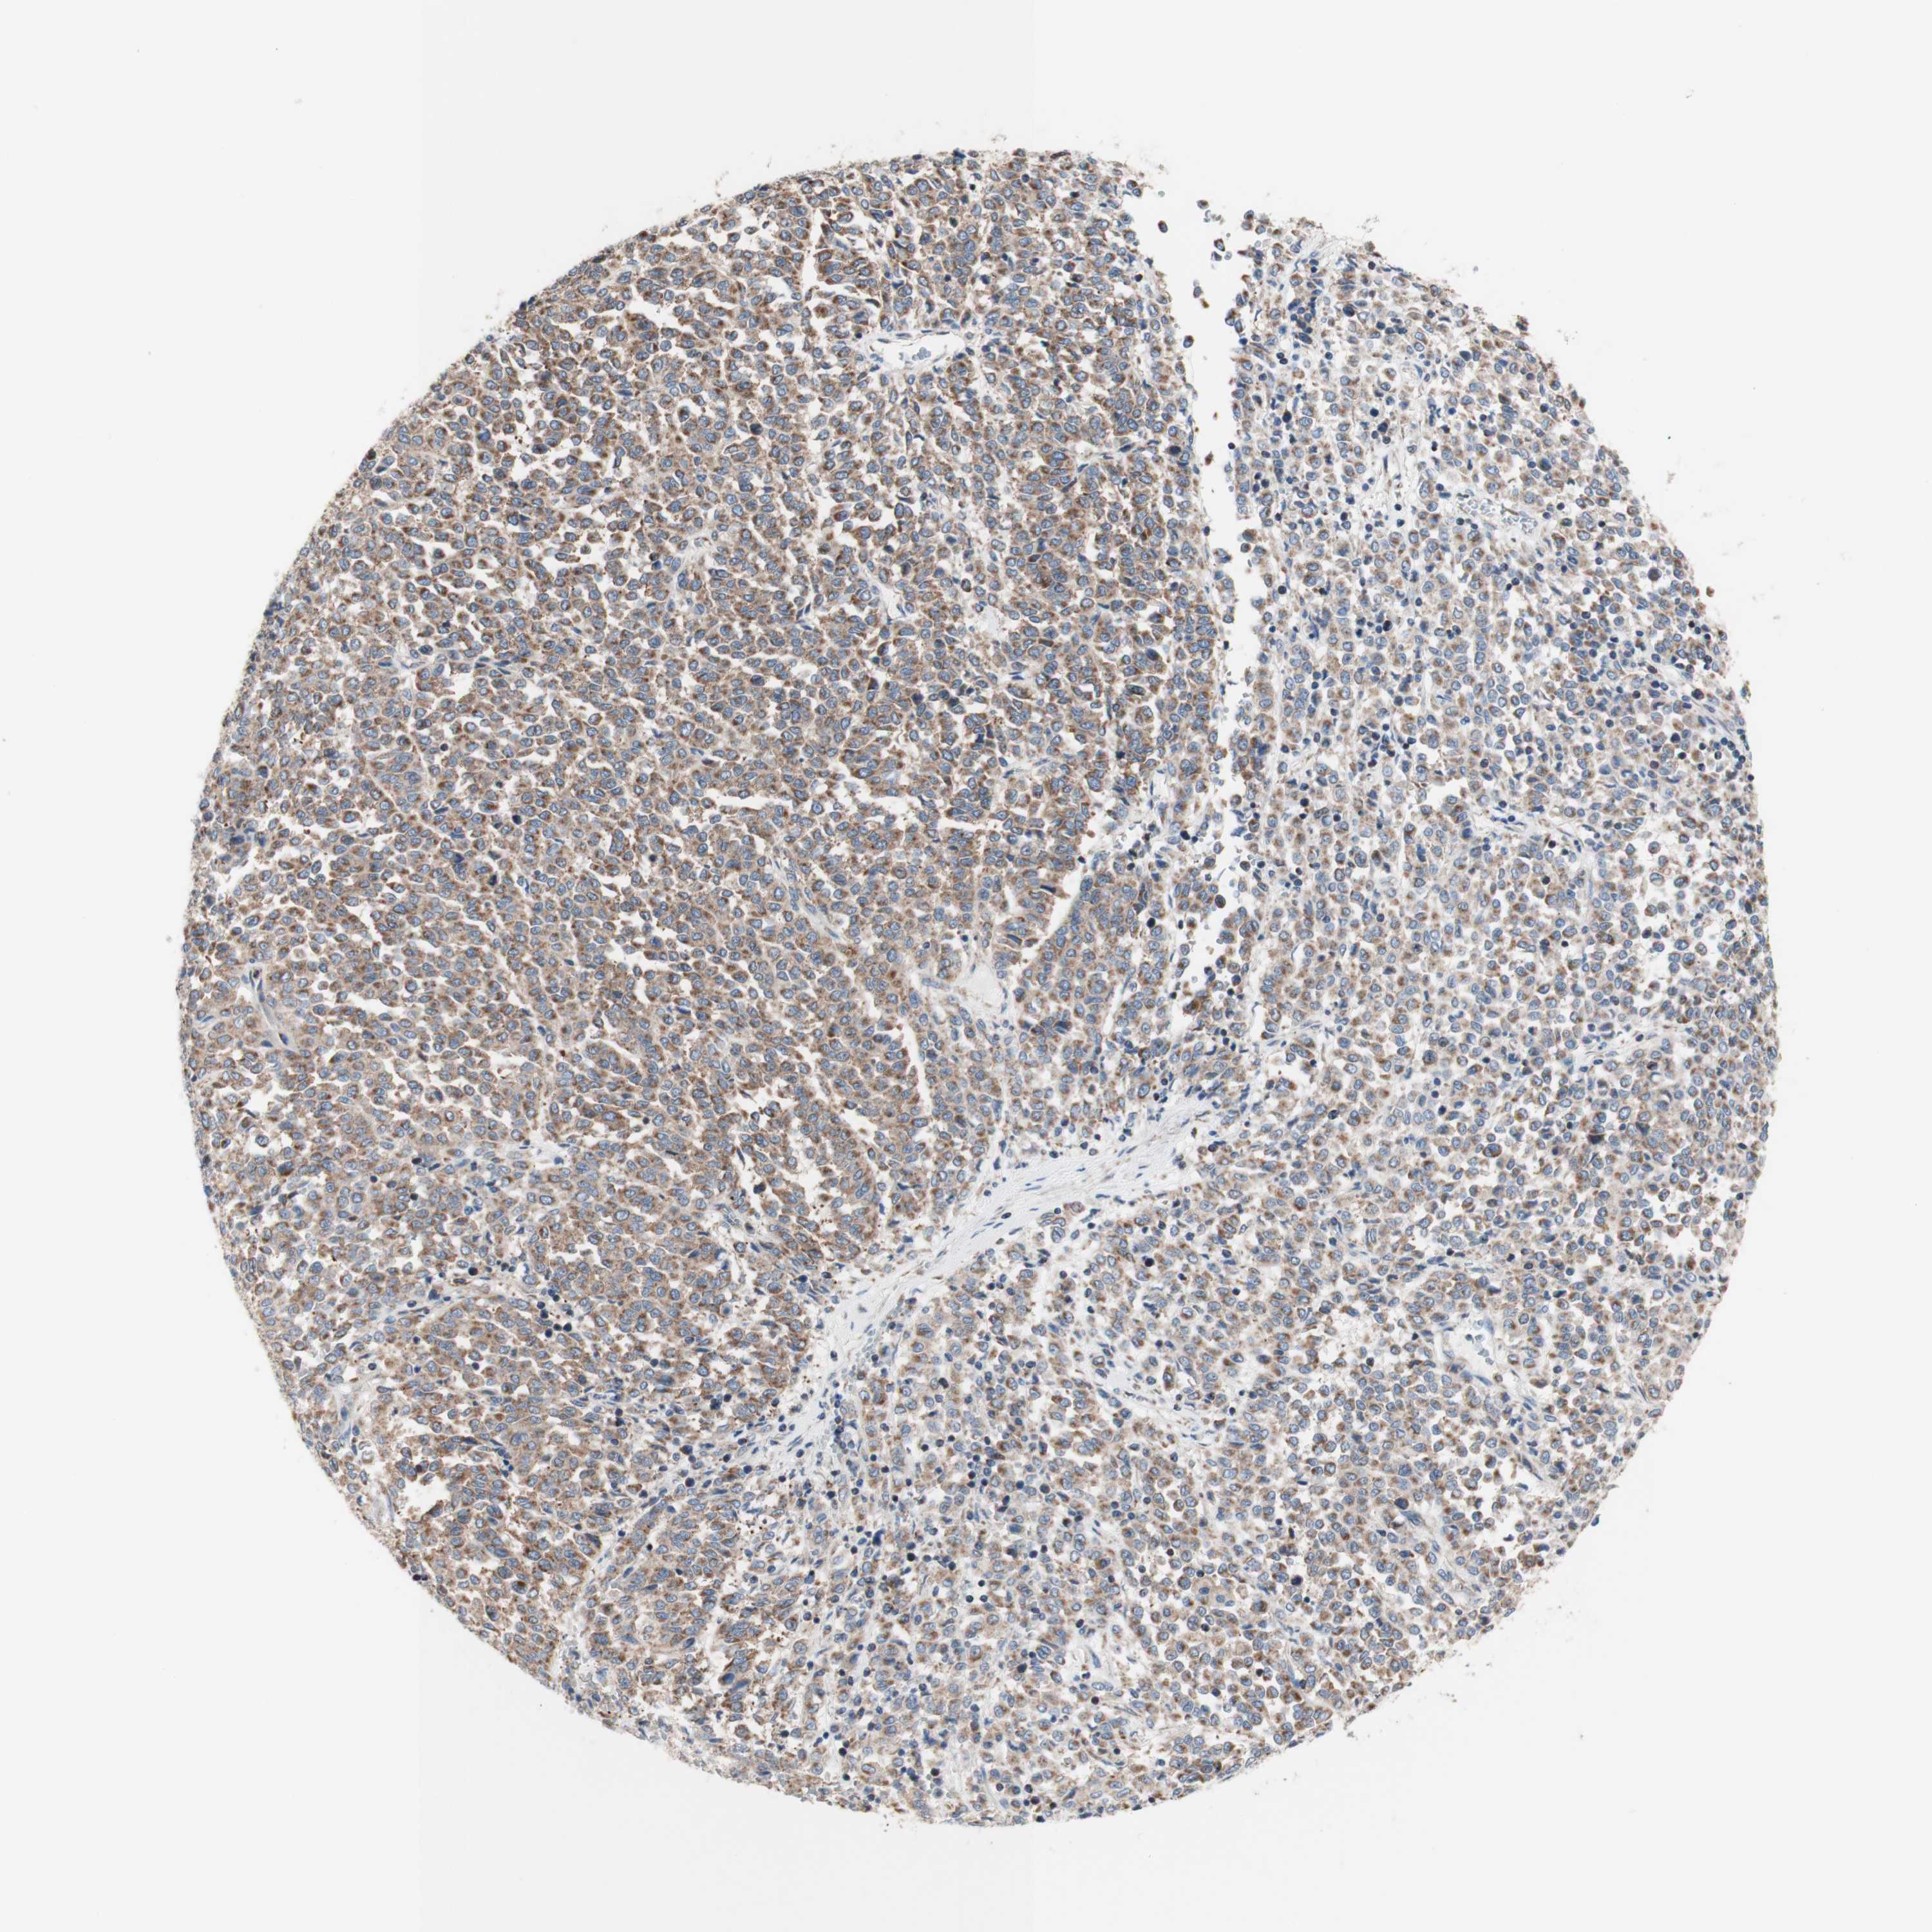

MELANOMA - Protein expressioni

A mouse-over function shows sample information and annotation data. Click on an image to view it in a full screen mode. Samples can be filtered based on level of antibody staining by selecting one or several of the following categories: high, medium, low and not detected. The assay and annotation is described here.

Note that samples used for immunohistochemistry by the Human Protein Atlas do not correspond to samples in the TCGA dataset.

Antibody stainingi

Antibody staining in the annotated cell types in the current human tissue is reported as not detected, low, medium, or high, based on conventional immunohistochemistry profiling in selected tissues. This score is based on the combination of the staining intensity and fraction of stained cells.

Each image is clickable and will lead to virtual microscopy that enables deeper exploration of all samples and also displays staining intensity scores, fraction scores and subcellular localization as well as patient and tissue information for each sample.

Antibody HPA050118

Antibody HPA056084

Antibody CAB012444

Staining

High

Medium

Low

Not detected

Intensity

Strong

Moderate

Weak

Negative

Quantity

>75%

75%-25%

<25%

None

Location

Nuclear

Cytoplasmic/membranous

Cytoplasmic/membranous,nuclear

Malignant melanoma, NOS

Malignant melanoma, Metastatic site